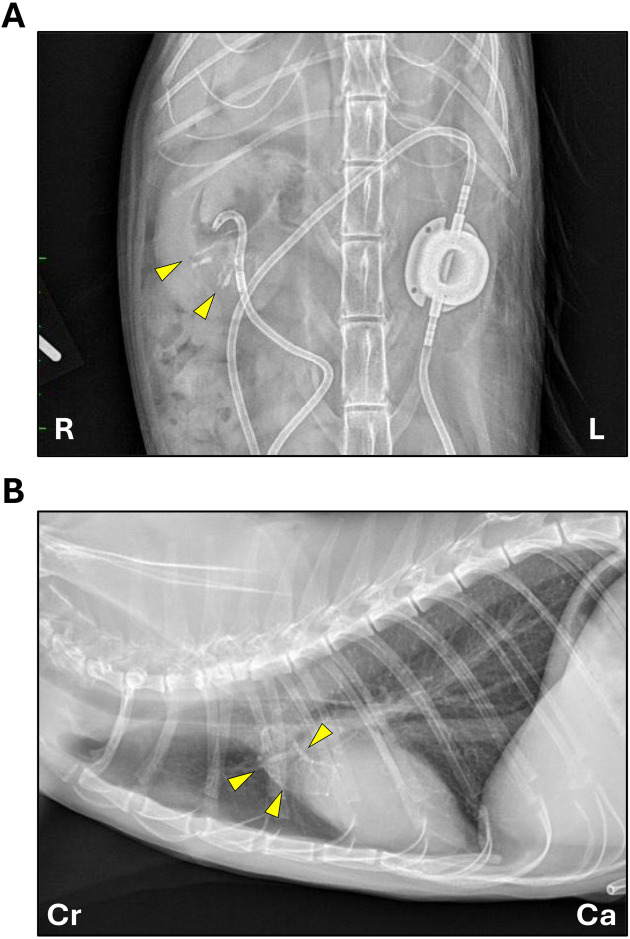

A 3-year-old neutered male mixed-breed cat was presented with right urinary tract obstruction caused by a urolith and severe atrophy of the left kidney. In the next year and a half, chronic kidney disease (CKD) progressed, and several masses were identified in the extremities, along with an ulcer on the tongue. Histologically, the extremity masses consisted of calcium deposits separated by fibrovascular septa, and the tongue ulcer showed severe neutrophilic infiltration with pervasive calcium deposition. These lesions were diagnosed as calcinosis circumscripta (CCs). Concurrently, multifocal mineralization of the aorta and of small- to medium-sized arteries in several organs indicated widespread vascular calcification. Both extremity and vascular lesions were likely secondary to the excessive calcium-phosphate product caused by CKD. Although CCs in either the extremities or tongue has been reported in cats, this case is notable for the presence of CCs in both extremities and tongue with systemic vascular calcification.